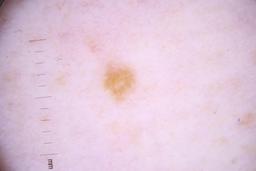

ISIC_4077341

- Challenge 2020: Training

Clinical

| Field | Value |

|---|---|

| acquisition_day | 1 |

| age_approx | 50 |

| anatom_site_1 | Trunk |

| anatom_site_2 | Anterior trunk |

| concomitant_biopsy | False |

| dermoscopic_type | contact non-polarized |

| diagnosis_1 | Benign |

| diagnosis_confirm_type | serial imaging showing no change |

| family_hx_mm | False |

| image_type | dermoscopic |

| lesion_id | IL_9238622 |

| patient_id | IP_1969685 |

| personal_hx_mm | True |

| sex | male |